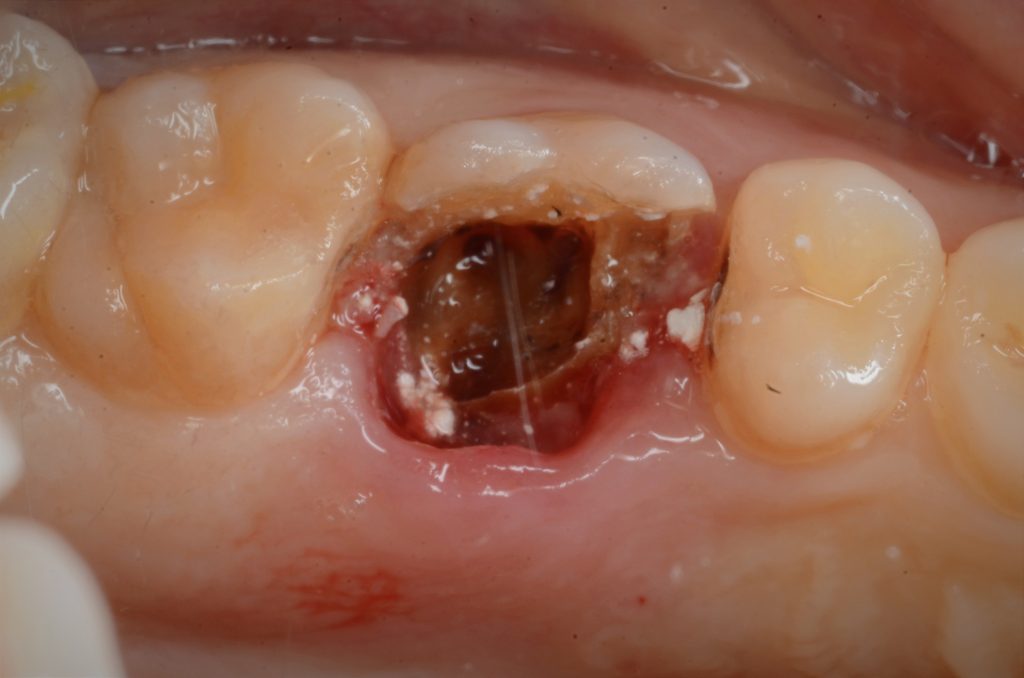

جاء المريض إلى العيادة بحاجة إلى إعادة حشوة السن رقم 26

بعد التشخيص بالأشعة السينية والأشعة السينية

لقد أظهرت نتائج سيئة وقنوات متكلسة

Preoperative

Preoperative x-ray